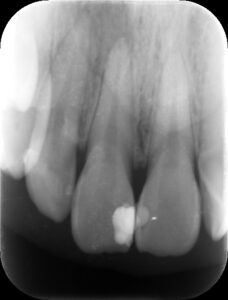

初診時レントゲン。上顎前歯の歯茎の腫れを主訴に来院。歯冠部に白い大きなレジン充填の跡が見られ、根尖部に黒いX線透過像を認める。